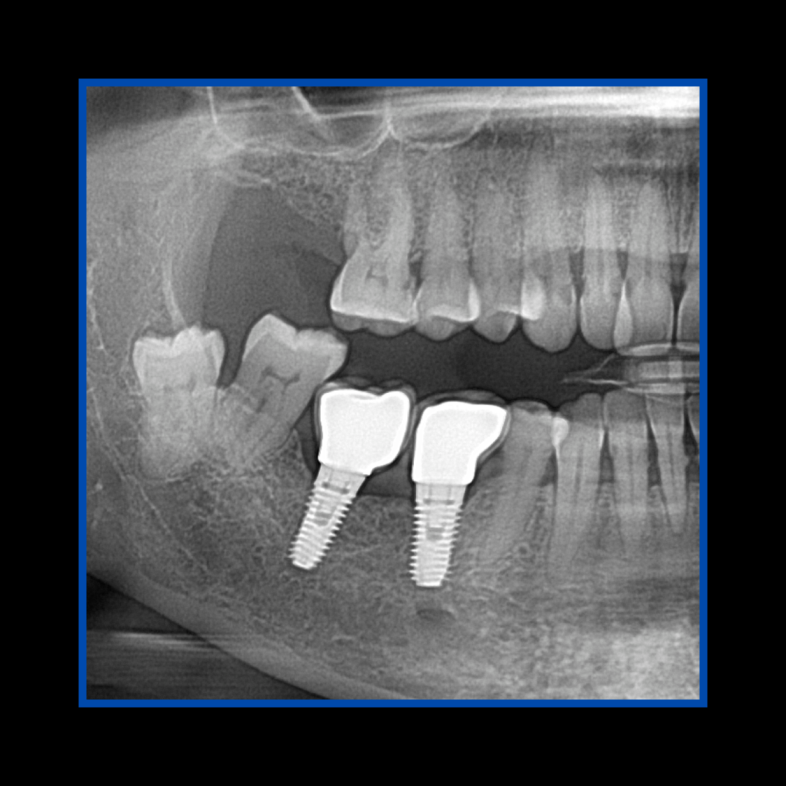

Diş çekiminin yıllar önce yapılmış olmasına bağlı olarak ince kemik varlığında implant ve kemik grefti uygulandı